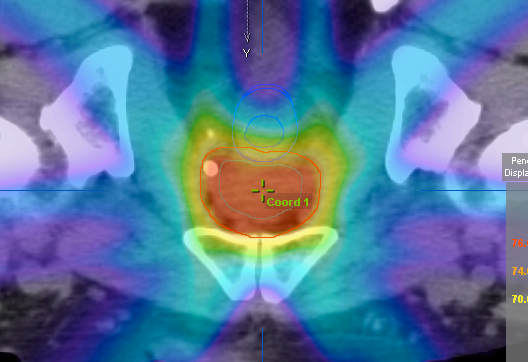

α)外照射療法:強度変調放射線治療(IMRT)

IMRT(intensity modulated radiotherapy)は患者さん毎に個別にコンピューターで治療計画と立て、より高エネルギーX線の強さを細かく制御することで腫瘍部分のみに放射線を集中させ,周囲正常組織への照射を軽減させる画期的な方法です。IMRTにより通常の放射線治療より多くの放射線を前立腺のみに照射することができ、周囲組織である直腸や膀胱への照射量を減らすことができるので効果が高まり、副作用が軽減できます。精密な線量計算、治療精度の確保が必須となるために、一部の施設でのみ行うことができる治療法です。当院では放射線治療科と連携し、IMRTで治療を行っています。

月曜日から金曜日まで週5日間治療し、約2ヶ月かかります。照射線量は74-78グレイです。1回の治療時間は10分〜15分程度で、外来通院で治療が出来ます。合併症は膀胱刺激症状(頻尿、排尿困難)、放射線性直腸炎(頻便、残便感、出血)、直腸潰瘍、尿失禁、性機能障害などがあります。

診断時のPSA値やグリソンスコアにもよりますが、通常、半年から2年間程度、内分泌療法を併用します。